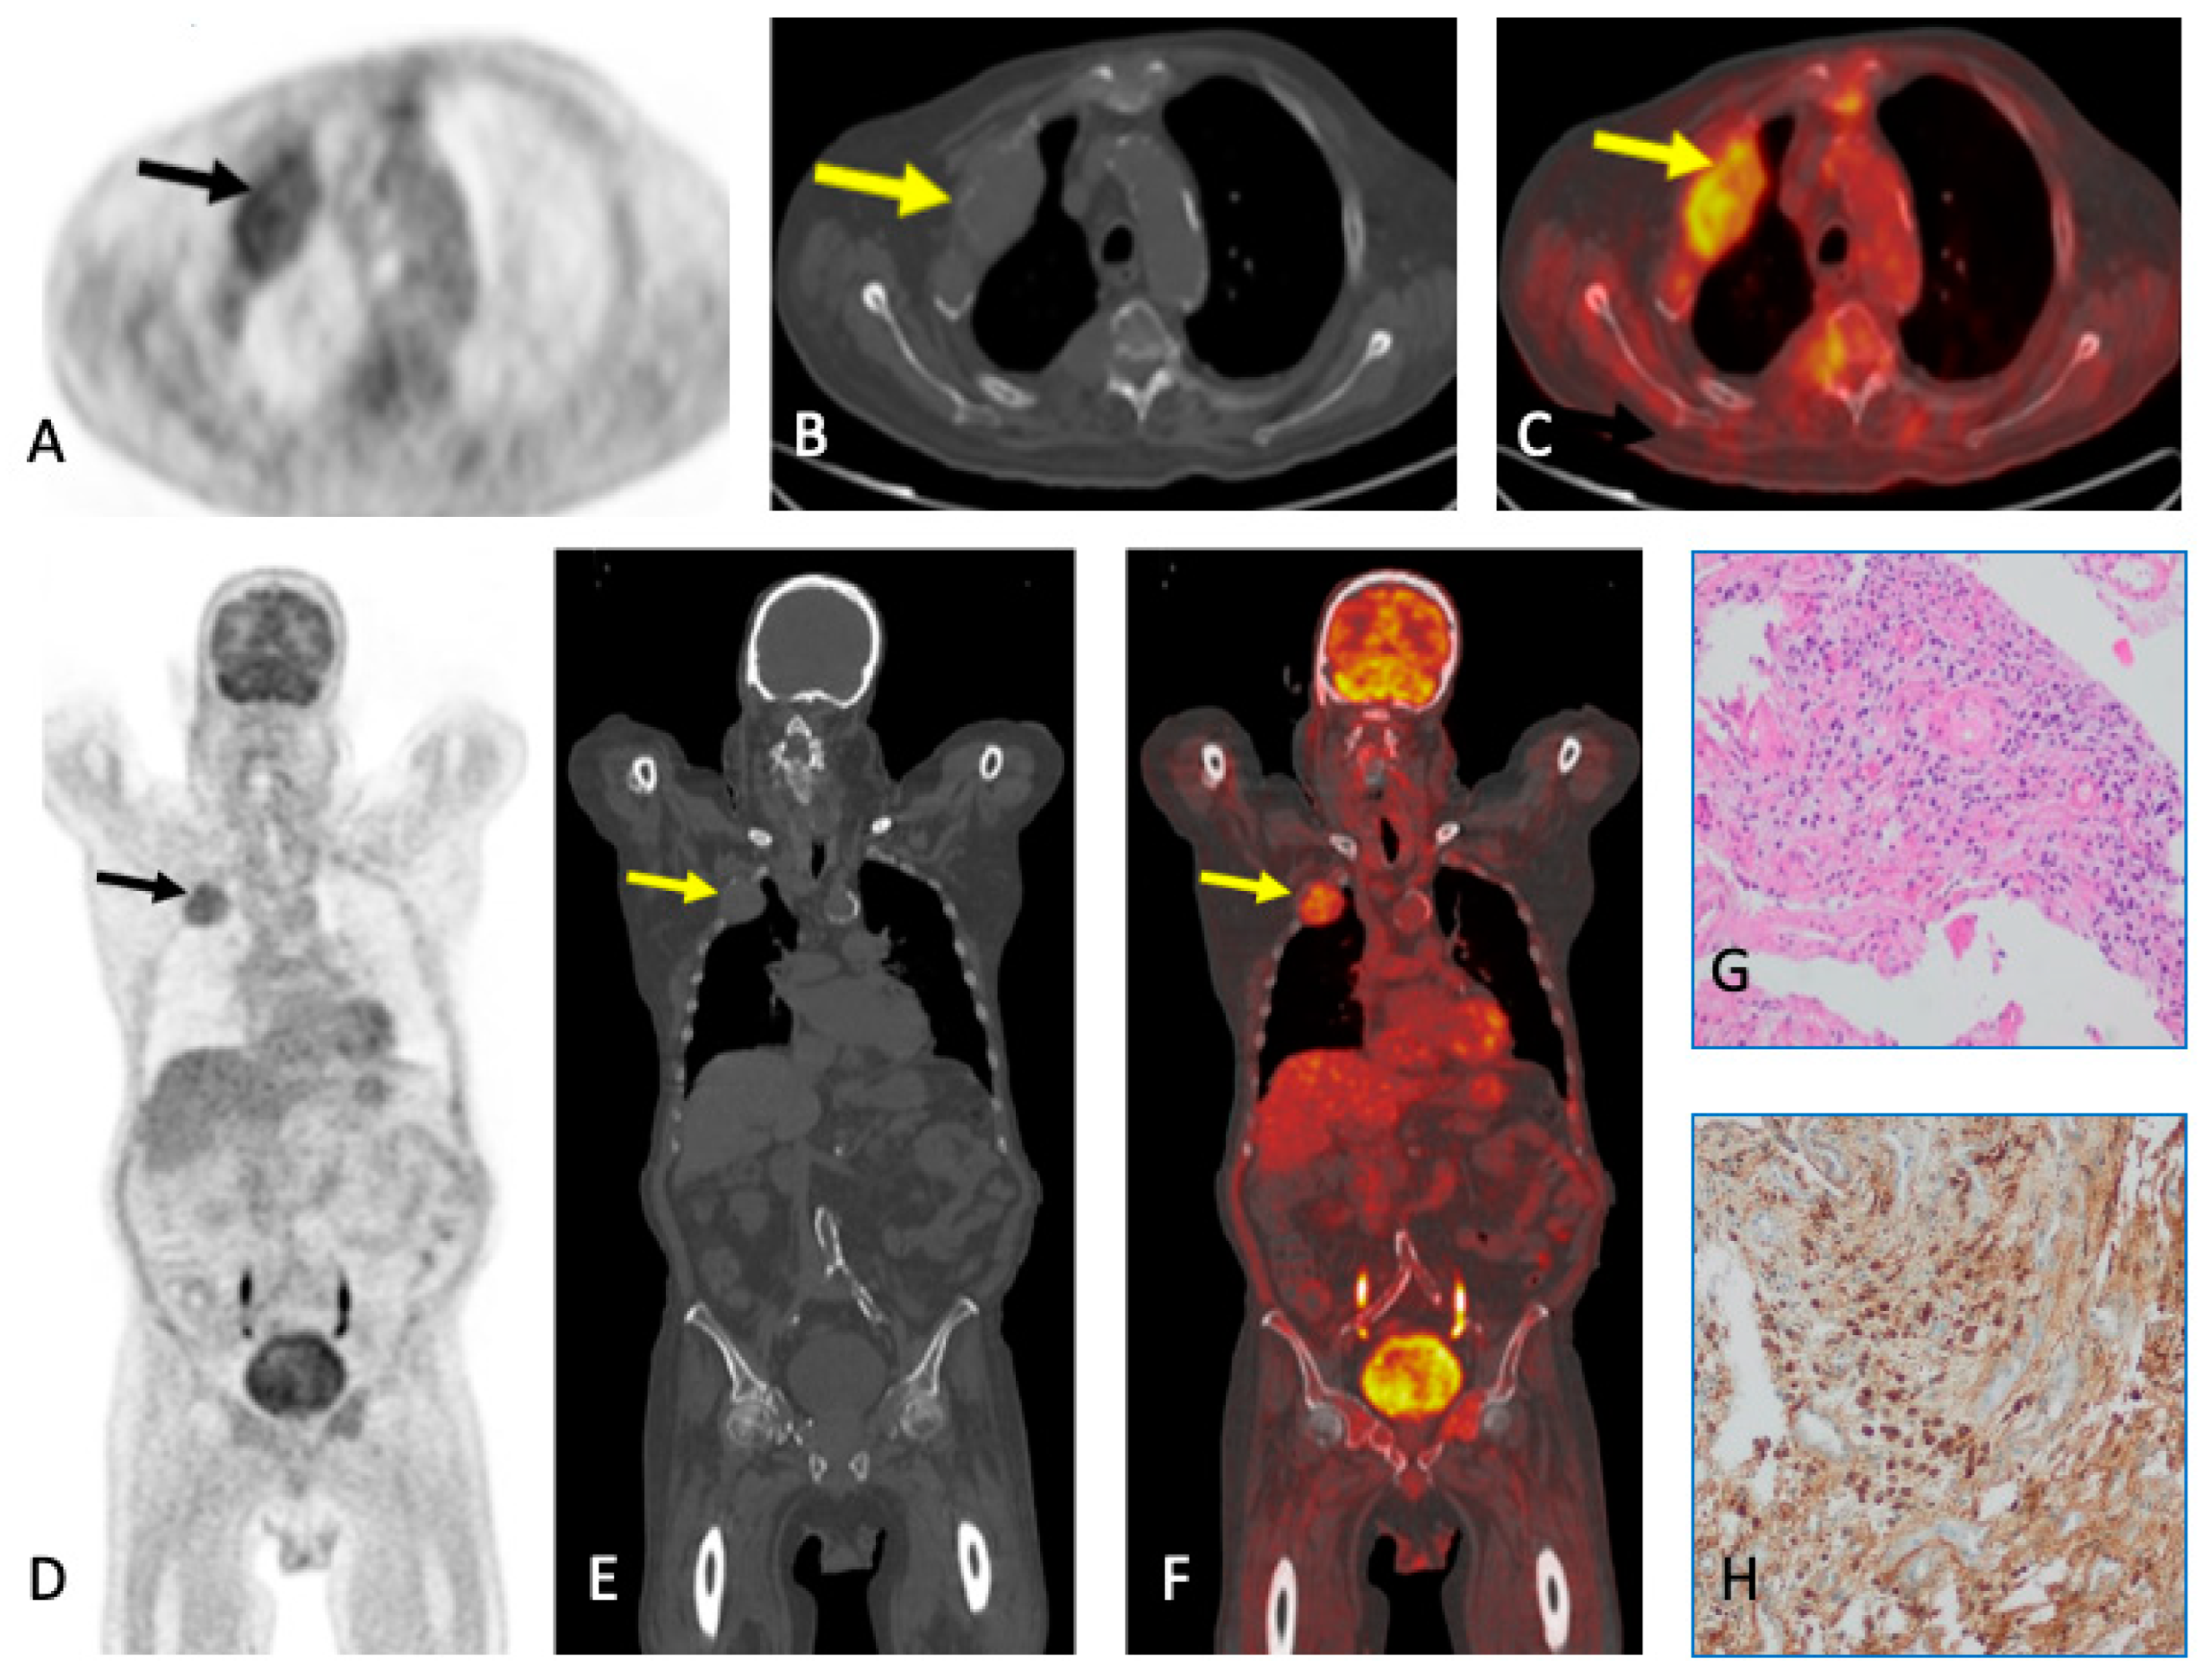

6. Plasmacytoma and Extramedullary MM